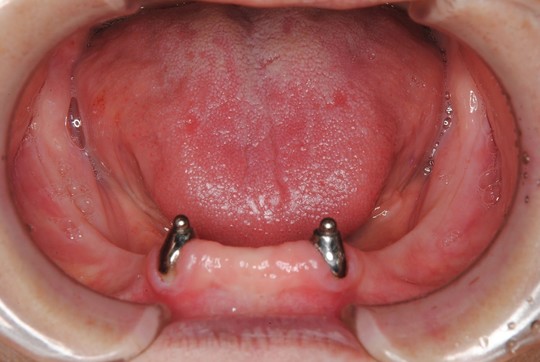

アタッチメント義歯(下顎義歯)

治療前

浮いたり外れたりしない下の入れ歯を製作して欲しいとのことで来院されました。

治療後

口の中で動きにくく外れにくい入れ歯ができました。

下顎義歯は残っている歯に「エラアタッチメント」

特殊な装置を組み込んで入れ歯の安定を図りました。